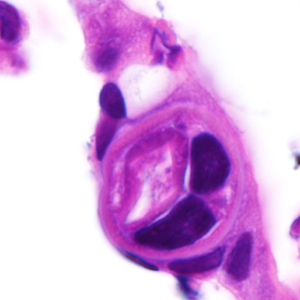

A 25-year-old male was hospitalized for Crohn’s exacerbation, duodenal outlet obstruction, and regional enteritis. He indicated that he has not had recent travel abroad. The patient underwent a gastroenterostomy and duodenal biopsy specimens revealed acute and chronic inflammation with crypt abscesses, focal ulceration, and reactive epithelial changes. Granulomata, epithelial dysplasia, and fibrosis were lacking. The attending pathologist also noted suspect parasitic organisms and the slides were sent to the state health department, which in turn forwarded them to the CDC-DPDx for diagnostic assistance. Figures A–F show what was observed on the slides received for testing. Figure A was taken at 100x magnification; Figures B–D at 400x magnification; and Figures E and F at 1000x magnification with oil. What is your diagnosis? Based on what criteria?

Figure C